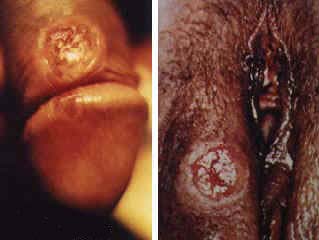

Sifilis

Ce este?

Sifilisul este o boala grava datorata unei bacterii. Se raspandeste prin

contact genital, anal sau oral cu o persoana infectata. Primul semn al acesti

boli este o ulceratie nedureroasa in locul prin care germenul a intrat in

organism. A doua faza apare peste mai multe saptamani si consta in aparitia

unor puncte rosi pe tot corpul. Sifilisul afecteaza intregul corp.

Cum

se depisteaza?

Fluide extrase din ulceratii se examineaza la miroscop. Se mai efectueaza si

analize ale sangelui.